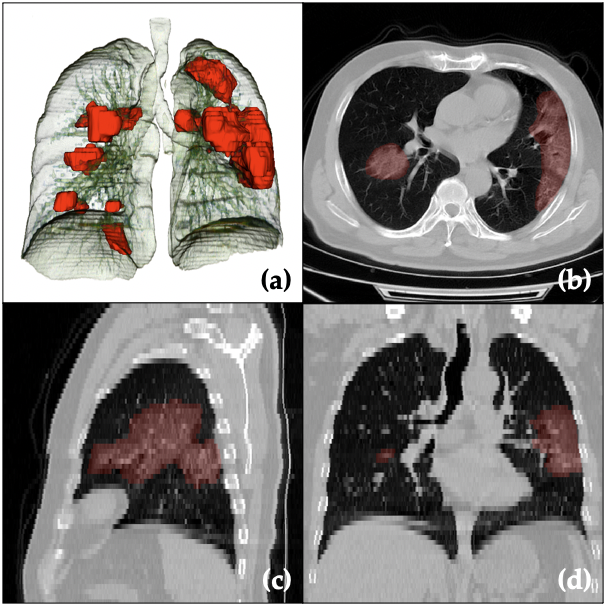

In this paper, we proposed a federated semi-supervised learning framework for COVID-19 affected region segmentation in 3D chest CT (3D visualization with airway and lung in Fig 9). The proposed framework is capable to grasp valuable information from the clients which only have unlabeled data. Meanwhile, the privacy of all patients has been preserved, and they do not need to share their own database for collaborating on joint model training. Moreover, after jointly training with supervised and un-/unsupervised clients, the generalizability has been improved for not only each client’s database, but also on the unseen data domain. We found out even the client with pure non-COVID database is able to help model training for COVID-19 affected region segmentation via false alarm rejection.

One thing to further clarify is that the aim of work is to segment the disease affected regions that is reflected in CT images, and the annotation is solely based on dataset consisting of COVID-19 cases. The “COVID-19 affected region” is identified as the abnormal regions in the context of these cases. Therefore, the model is not trained to discriminate against other type of abnormalities, e.g. other pneumonia or cancer. From a “pipeline” point of view, additional classification to tell the difference can follow the proposed segmentation method, but will need additional data and annotations. To give an example, we used our trained network to perform inference on LIDC dataset [2]. Fig. 8 showed four different cases of abnormalities captured by our model on LIDC images: 1. solid nodule, 2. mixed solid and ground glass nodule, 3. ground glass nodule, and 4. other abnormal pattern. As nodules have similar appearance in CT as abnormalities caused by COVID-19, those regions are detected.

Refer to caption

Figure 8: Model performance on LIDC dataset, capturing solid nodule (1, 2); ground glass nodule (2, 3); and other abnormal patterns (4).

Figure 9: Visualization of the COVID-19 affected region segmentation/prediction (red regions) together with lungs and airways (a) in 3D space, and (b,c,d) in different (axial, sagittal, coronal) planes of a raw CT image. Note that slice thickness is 5 mm (as compared with 0.8 mm in-plane), which is the case for most images in this work.